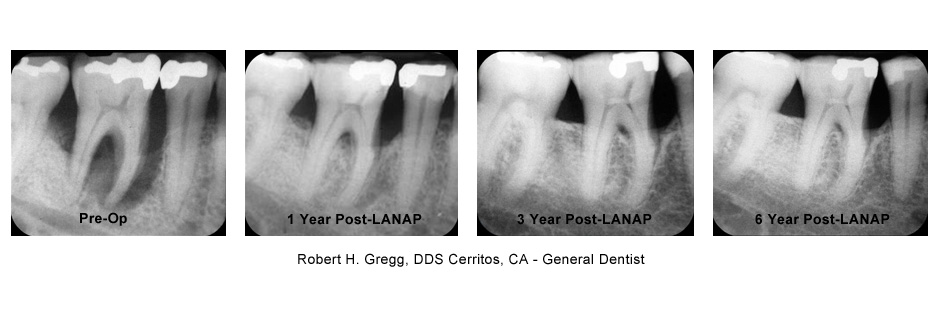

Traditional gum surgery involves cutting away some of the gum tissue, and reshaping the bone underneath. LANAP is a progressive technique using a specialized laser to destroy the bacteria that cause the disease, and alter the tissue so that it has the opportunity to heal. The use of the laser is less invasive than traditional scalpel surgery, and results in a much faster and less painful recovery.

As the gums heal, the teeth will shift, and your bite will need to be adjusted several times over the first few weeks, even for the first year and beyond. Although it seems counter-intuitive, inadequate adjustment is what is usually responsible for soreness or sensitivity following LANAP.

Professional cleaning is recommended every three months for the first year, and re-evaluation of your condition will be done at the twelve month visit. Most people with gum disease remain at risk for the rest of their lives, and would benefit from having their teeth cleaned every three months indefinitely.